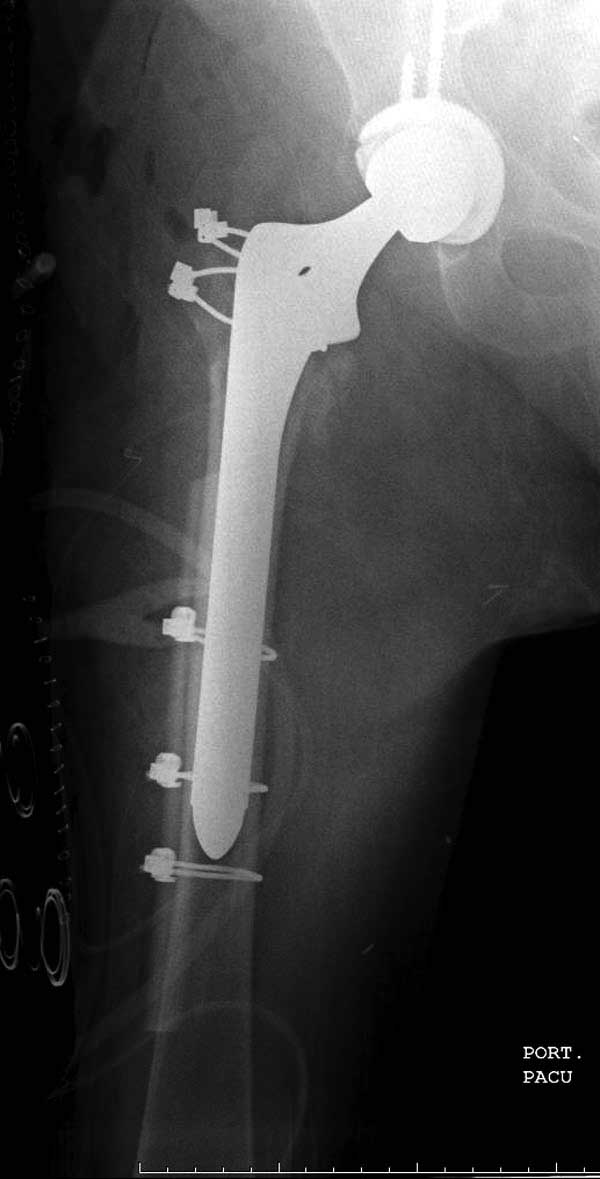

Такие “чужие осложнения” встречаются у всех и представляю банальный случай, который шаг за шагом показано как перерос в более сложный процесс... Больная 70 лет, множественные ко-морбидности, чрезвертельный перелом первоначально фиксирован Гамма 3. Осложнение в течение 6 недель, ревизия тотальной артропластикой и во время установки ножки обнаружена трещина диафиза (17), из малого доступа фиксация алло-графтом.

Обычно после чрезвертельных переломов, за исключением молодых, у пожилых остается нестабильность при движении. Часто падают и после 3х мес. в результате падения обнаружен перипротезный перелом (22-23), который зафиксирован Синтез пластиной.